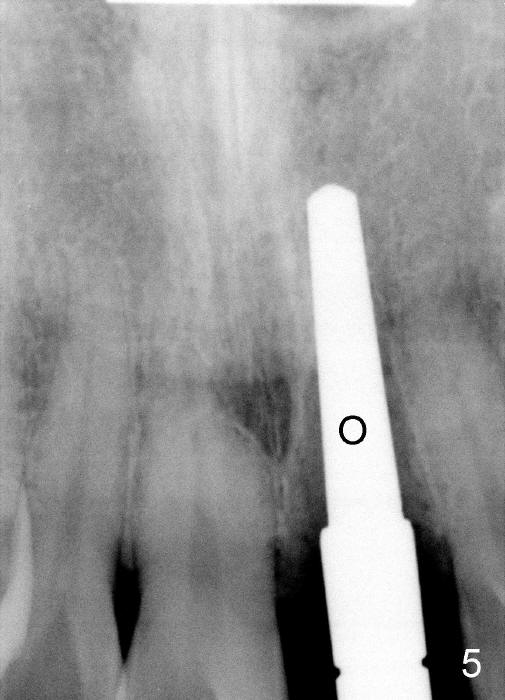

The upper right central incisor (Fig.1: #9) fractures subgingivally due to trauma for a 40-year-old man. The incisive canal is large (I) and close to the root of the central incisor. After extraction, the osteotomy (Fig.3b, 4: O) is made with 2 mm pilot drill (Fig.2: D) on the lingual wall (Fig.3a: L) of the socket (Fig.3a: S). To push the incisive canal mesially, the osteotomy is enlarged by 3.5x21 mm and 4x21 mm tapered osteotomes (Fig.5,6: O). Due to the lingual slope (Fig.7a arrow), the osteotome (blue outline) starts to deviate bucally. To reduce this tendency, the coronal portion of the lingual slope is removed (Fig.7b: yellow circle). The final implant (4.5x20 mm) is able to be placed as lingually as possible (Fig.7c, 8).

Bone expansion allows the implant (Fig.9 I) to have primary stability (insertion torque between 50 and 60 Ncm), since the cortex of the incisive canal is apparently intact. Allograft is placed in the labial gap (Fig.10, 11 *) following installation of the abutment (A). Finally an immediate provisional (Fig.10,12 P) is cemented. Fig.13,14 are taken 8 days postop. The patient returns 3 months postop (Fig.15,16). Osteointegration appears to have occurred (Fig.15 arrowheads) and is more obvious 9 months postop (Fig.17).